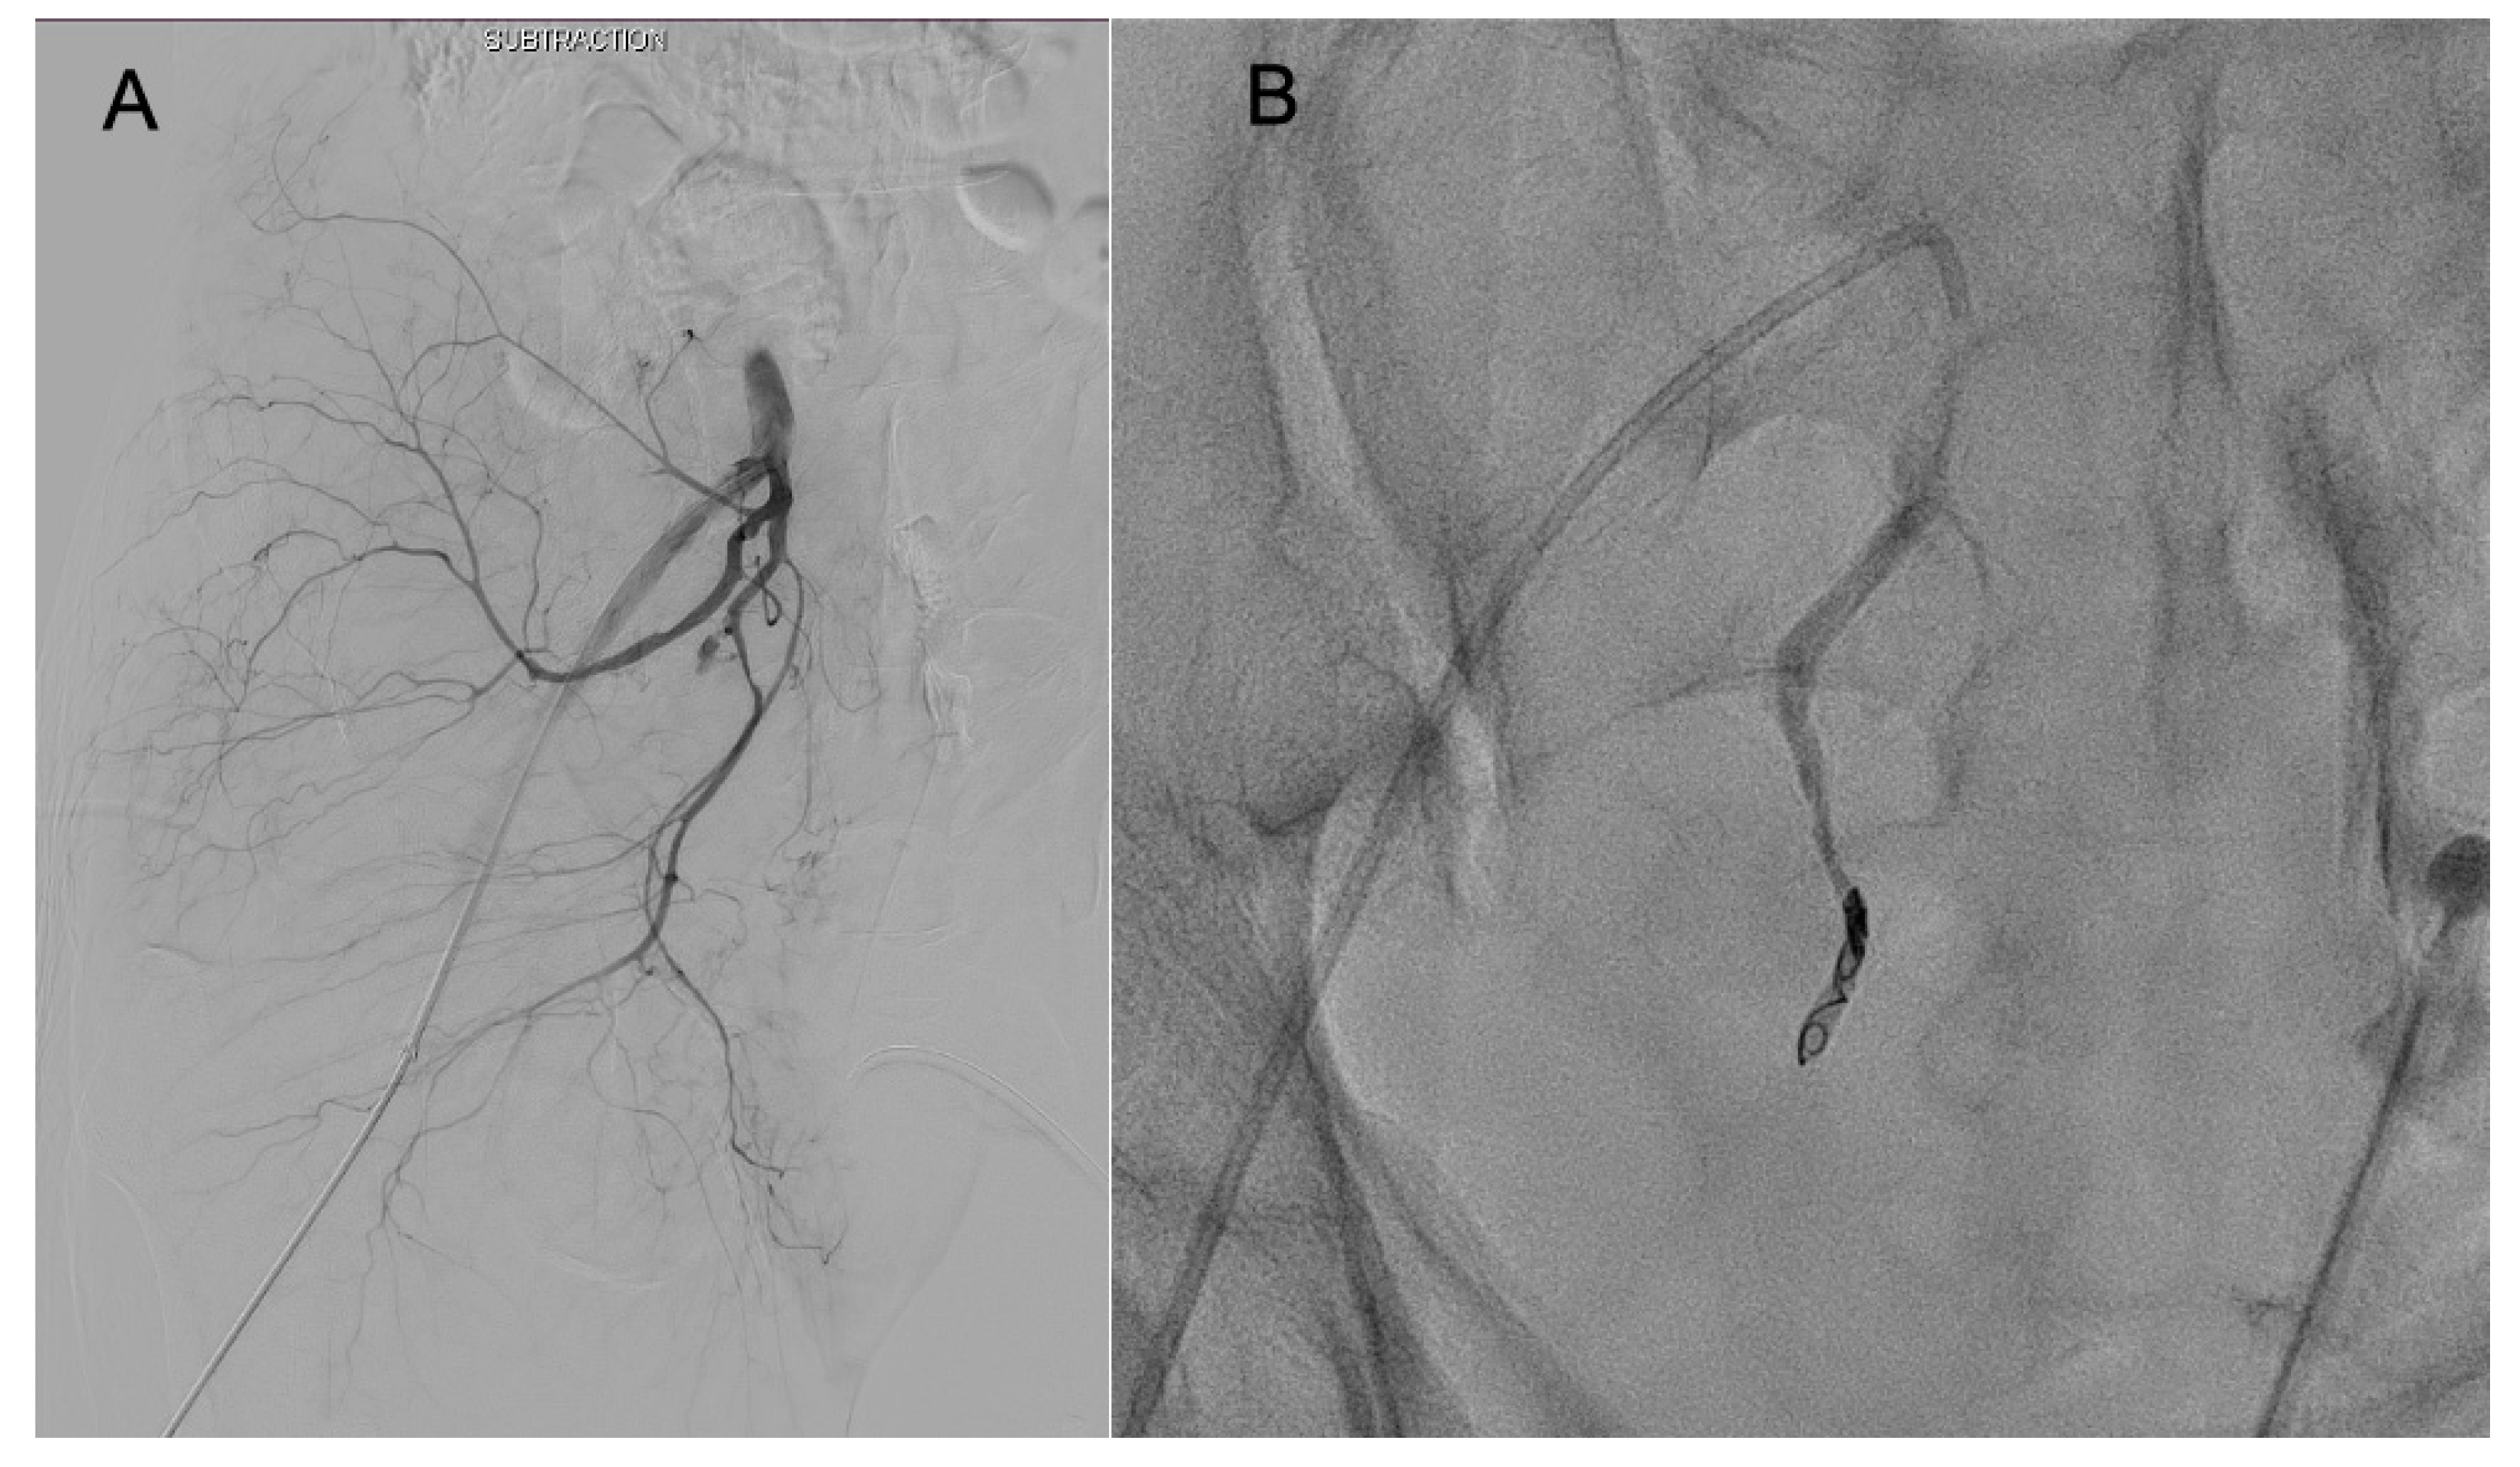

2.4. AE